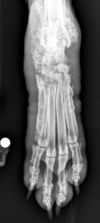

What is shown in these radiographs?

A

hip dysplasia

-minimal coverage of femoral head

-flattened, sclerotic femoral head

-no femoral neck present

-osteophyte formation and sclerosis